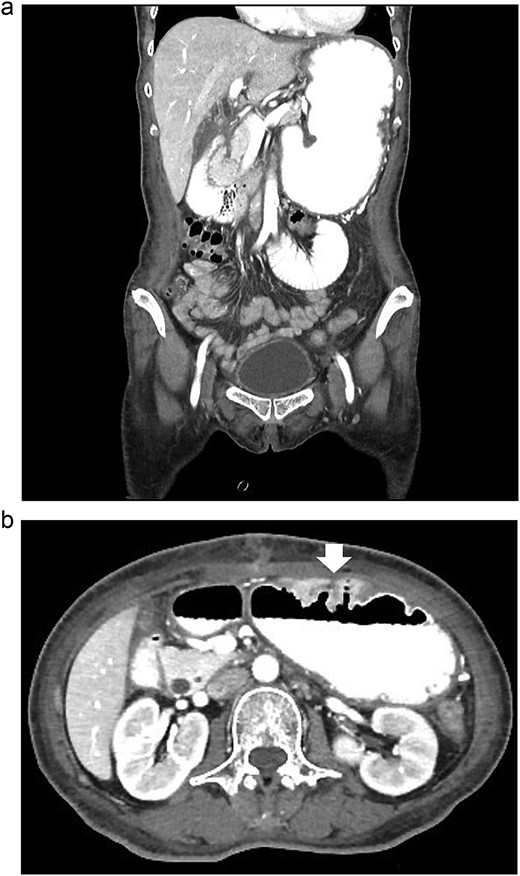

According to these clinical and radiological finding, concern of recurrent gastric outlet obstruction has been raised. Therefore, the computed tomography (CT) scan of the abdomen was performed and showed gastric and afferent limb dilatation, no oral contrast filling in efferent limb and collapsed remaining small bowel loop just distal to gastrojejunostomy anastomosis (Fig. 1). The CT scan findings was afferent limb syndrome associated with efferent limb obstruction due to gastrojejunostomy anastomosis angulation and kinking. The patient was rehydrated with intravenous fluid. Nasogastric tube was placed for decompression. After 5 days of conservative treatment, the abdominal distention was improved but the content from nasogastric tube was continuingly 800–1000 ml per day. Upper endoscopy under general anesthesia was performed for definite diagnosis and chance for endoscopic treatment. It showed patent gastrojejunostomy anastomosis but the both proximal afferent and efferent limb were angulated. Endoscopic dekinking was performed by gentle passage of the endoscope tip across the angulated segment until the intraluminal intestinal segment distal to the obstruction point was reached (Fig. 2).

The CT scan of abdomen: (a) coronal view showed dilated stomach and afferent limb, (b) axial view showed gastrojejunostomy anastomosis angulation and kinking (arrow).